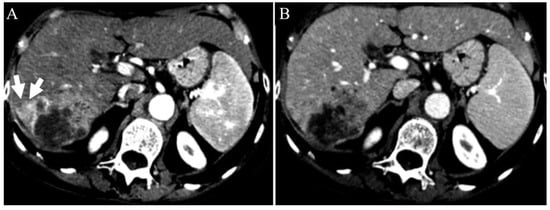

| Irregular margins | 21 (58.3%) | 26 (47.3%) | 0.391 |

| TTPVI | 14 (38.9%) | 11 (20%) | 0.058 |

| Peritumoral enhancement | 4 (11.1%) | 6 (10.9%) | 1.000 |